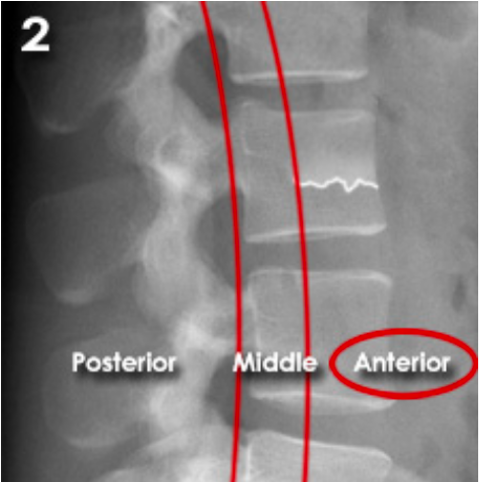

Lumbar three column model

Divides the spine into three columns: anterior, middle, and posterior

Used to determine the stability of thoraco-lumbar spine fractures

severity depends on how many columns are implicated

If spinal instability is suspected further imaging with CT or MRI should be considered

ANTERIOR (Stable):

Anterior compression injury

e.g. compression fractures (most common)

between the anterior longitudinal ligament to the middle of the vertebral body